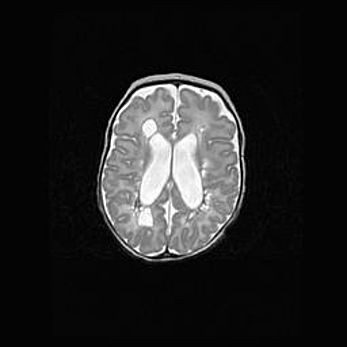

Множественные кисты обоих полушарий головного мозга, наибольшая из них в правой затылочной области. Ассиметричная атрофическая гидроцефалия.

Возраст: 7 месяцев

Вес: 5660 г

Пол: мужской

Окружность головы: 41,5 см

Срок гестации: 28-29 недель

Кисты головного мозга развиваются в результате многоочаговых некрозов вещества мозга и возникают вследствие перенесенной перинатальной инфекции, менингитов, энцефалитов, асфиксии, родовой травмы, расстройств мозгового кровообращения различного генеза. Образованию кист в веществе головного мозга плодов и новорожденных способствуют такие факторы, как высокое содержание в нем воды, недостаточная (или отсутствие) миелинизация и слабая астроглиальная реакция на повреждение.

Кисты могут сочетаться с гидроцефалией и другими поражениями головного мозга.